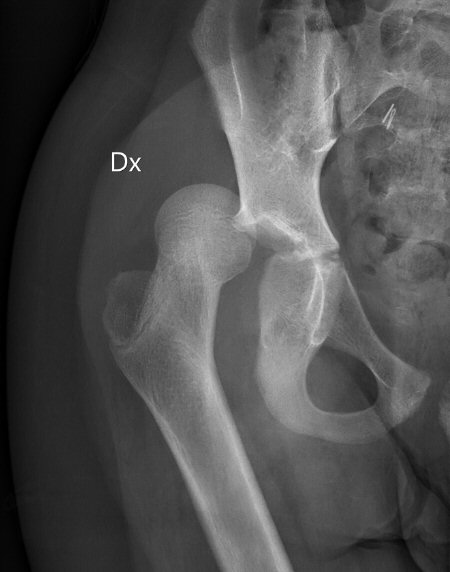

Exempel på höft hos 10-åring som luxerat efter lindrigt trauma

Vid ålder < ca 10 år kan det räcka med lindrigt trauma, exempelvis fall vid idrottsutövande, vid ålder > 10 år krävs ofta högre energi. [1, 2]

- Synlig felställning, ofta förkortat ben med höft i flektion, adduktion och inåtrotation. [1]